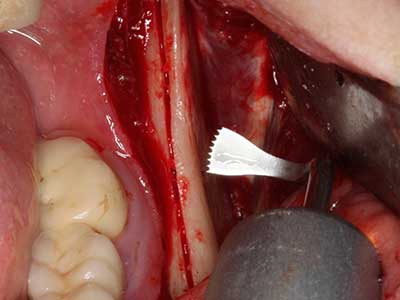

As shown in the past, basically any bone surgery procedure represents a possible indication for piezosurgery. Thus preparation of the mobile segment in distraction osteogenesis (Fig. 23-25) and sandwich osteotomy uses special attachments without endangering the blood supply to the crestal section, which is essential for the success of both techniques (Gonzalez-Garcia, Diniz-Freitas et al. 2008).